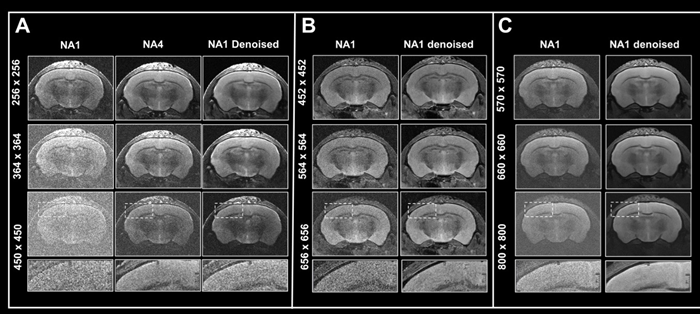

Boosting resolution

Figure 6. Boosting resolution. Ex vivo T2-weighted TurboRARE data of a fixed mouse head acquired at A) 3 Tesla, B) 7 Tesla, and C) 9.4 Tesla. All images were acquired with 0.8 mm (A) and 0.7 mm (B, C) slice thickness and with a field-of-view of 20 x 20 mm2 and the given matrix size using either no averaging or acquiring 4 averages. Images were reconstructed with no denoising (NA1 and NA4), or after denoising (NA1 Denoised) using a network Large, applying a pre-denoising level of 50 % and denoising level of 70 %. Image Credit: Bruker BioSpin Group

In Fig 6, axial T2-weighted TurboRARE images of a fixed mouse head taken at various field strengths are compared. Images were obtained with a fixed field-of-view of 20 x 20 mm2, slices that were 0.8 mm (3 Tesla) and 0.7 mm (7 and 9.4 Tesla) thick, and changing matrix sizes to produce images with various spatial resolution.

For images acquired at 3, 7, and 9.4 Tesla, the matrix sizes were raised by up to 1.8, 2.6, and 3.1 (compared to the reference protocols' matrix size of 256). These resolution upgrades cause a reduction in SNR for each image.

The loss in SNR can be accounted for by averaging, therefore extra data was collected using four averages.

A comparison of non-denoised averaged images and single averaged images that were denoised demonstrates that denoising reduces increased image noise at higher resolutions and produces images of comparable quality to those generated through averaging.

The advantages in image quality from denoising are greater with data recorded at 3 Tesla, when increasing resolution provides images that are more difficult to interpret, as opposed to data acquired at 7 and 9.4 Tesla, where SNR is naturally higher.

Nonetheless, images taken at 7 and 9.4 Tesla benefit significantly from denoising during reconstruction since the intrinsic higher SNR of these images may be used to pick smaller voxel sizes.

This shows that denoising allows for better resolutions within a given unit time by reducing the requirement for averaging. This can also be useful when averaging is neither desirable nor practical.